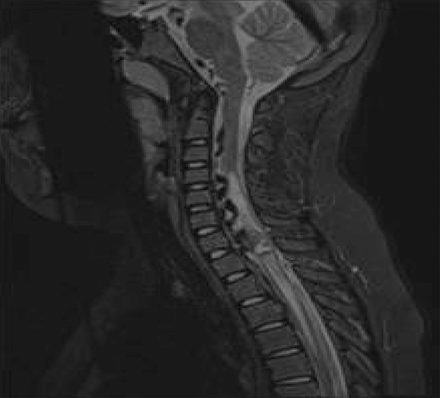

图1

核磁共振成像

搅拌脂肪饱和t2加权MRI矢状面显示线扩张和水肿(白色信号从C4 T4)二级脊椎硬脑膜动静脉瘘。信号波形的排水静脉被认为在前面(黑色)扩展向头部地。